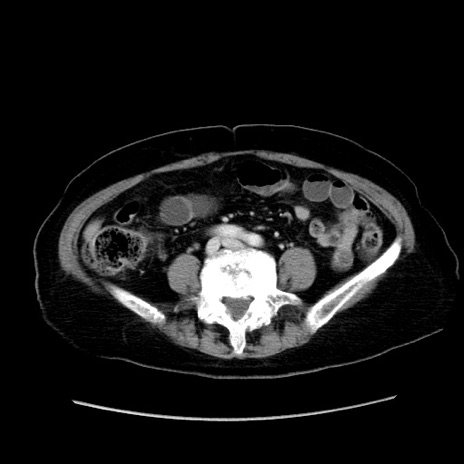

症例19(横断像)

【症例】80歳代女性

【主訴】下腹部痛

【現病歴】約8時間前より下腹部痛の出現あり、救急外来受診。

【既往歴】両側付属器切除

【身体所見】意識清明、下腹部正中に手術痕あり、その部位に一致して圧痛と反跳痛あり。腸蠕動音は亢進。

【データ】WBC 9300、CRP 0.15